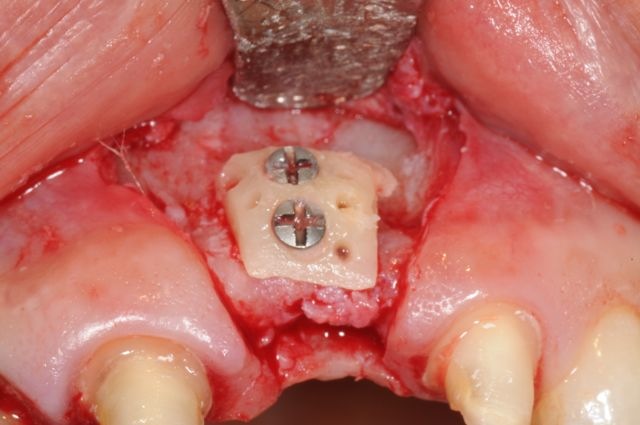

İrəli dərəcədə sümük itkisi mövcud olan, xüsusilə üst çənə ön bölgə və ya alt çənə arxa bölgələrində dental implantların funksional və estetik olaraq uyğun pozisiyada yerləşdirilməsi əksər hallarda ciddi bir problem olaraq qarşımıza çıxır. Problemin həlli əksər hallarda mövcud olan defektin sümükartırma metodları ilə bərpa edilməsi vasitəsilə həyata keçirilir. Bu məqsədlə fərqli metodlar, müxtəlif materialların tətbiqi ilə icra olunur.

Bərpa texnikasının müəyyən edilməsi, sümüyün hansı bölgədə, hansı miqdarda itirilmiş olmasına bağlı olaraq müəyyənləşdirilir. Bərpa üçün tətbiq edilən sümük materialları pasiyentin öz donor bölgələrindən xüsusi metodlarla qazanılmış sümüklər, o cümlədən digər fərdlərdən alınmış və xüsusi qaydada hazırlanmış materiallar, heyvan mənşəli sümükəvəzləyici materiallar və sintetik materiallar olaraq ayrılır.

Bərpa zamanı yerinə görə bu materiallar ya ayrı-ayrılıqda, ya da kombinə olunmuş şəkildə tətbiq oluna bilir. Gündəlik təcrübədə həmçinin pasiyentdən götürülmüş qan nümunələrindən alınmış yüksək bərpaedici xassəyə malik materiallar (PRF) da uğurla tətbiq olunur. Sümükartırma metodlarının tətbiqi sayəsində, çənədə implantların yerləşdirilməsi üçün yetərsiz sümük həcmi olan bölgələrdə sümük miqdarı yetərli duruma gətirilir, uyğun boy və diametrə uyğun implantlar uğurla tətbiq olunur.